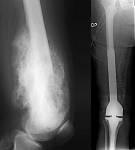

- Resection of benign and malignant tumors of the bone and soft tissue

- Reconstruction of bone defects by biological procedures (from spongiosaplasty to bone transfer)

- Tumor total endoprosthesis (TEP) of all large joints and bones